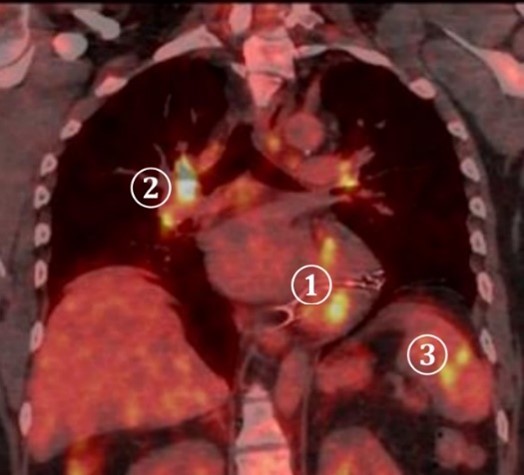

För närmare kartläggning av inflammationens utbredning utförs PET-DT

Tolka bilderna. Vilka anatomiska strukturer ”lyser” (inflammation/ämnesomsättning)?

Vilka diagnoser överväger du? Vad blir nästa steg?